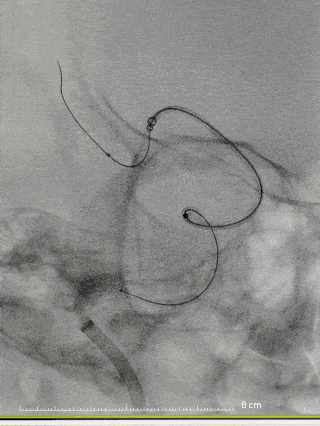

手术过程

图4右颈内动脉海绵窦段起始部类圆形瘤样扩张,最大约19mm╳14mm,瘤颈约14mm,瘤内射流明显,载瘤动脉远端5mm,近端4.5mm。

8F常规指引到右颈内动脉开口做近端支撑。Synchro 0.014 200微导丝及XT-27微导管引导CAT 5导管同轴越过右颈内动脉瘤至右大脑中动脉M1。由于动脉瘤颈较大,微导丝引导XT-27微导管,无法直接通过,采用瘤内成袢技术通过。选取Surpass Streamline 5mm╳30mm经CAT 5导管释放,并行微导丝及CAT 5导管按摩。

图5